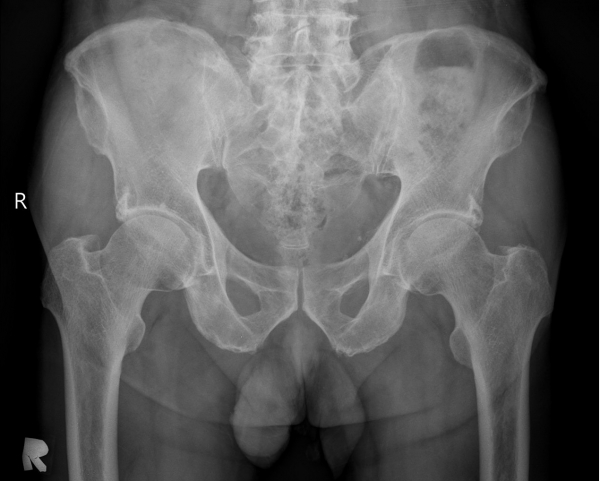

[¾ûµ¢ÀÌ] °í°üÀý Ãæµ¹ÁõÈıº¿¡ÀÇÇÑ È°¾×¸·¿° ÁÖ»çÄ¡·á

´Ü¼ø¹æ»ç¼±°Ë»ç